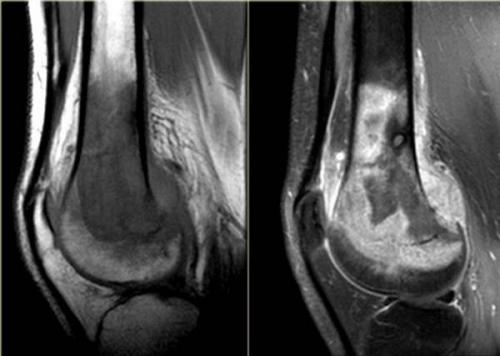

МРТ применяют в диагностике новообразований: кист, доброкачественных и первичных злокачественных опухолей, метастазов. В отдельной группе - сосудистые патологии, нарушения лимфотока, иннервации суставов и окружающих мягких тканей.

Остеосаркома коленного сустава на МРТ